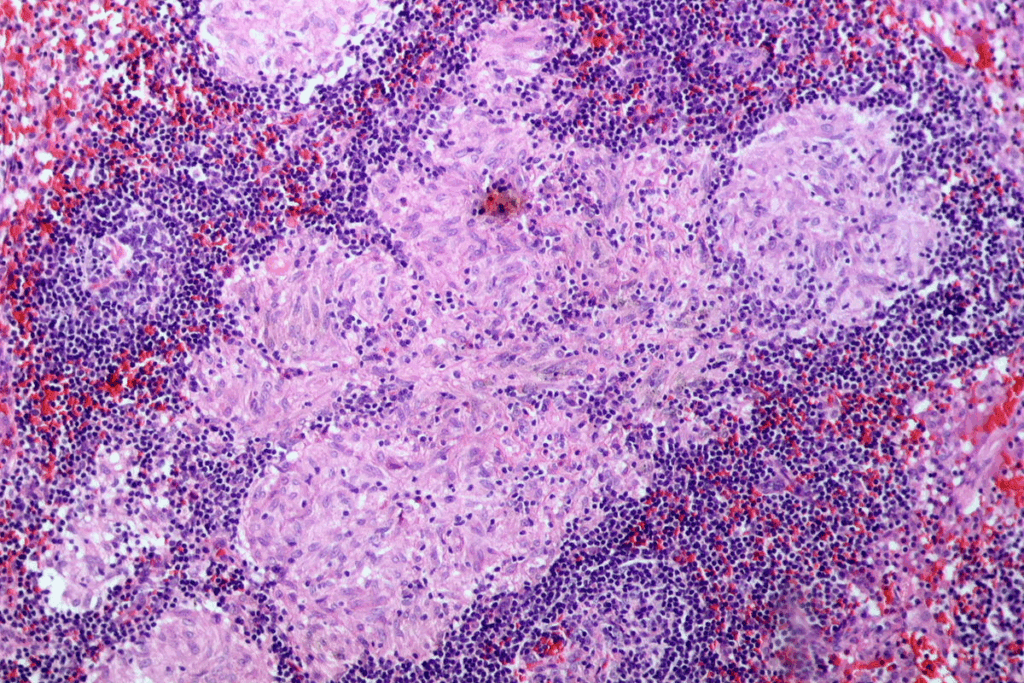

Types of Mouth and Oral Cancers

Oral cancer isn’t just one disease. It’s several types that can hit different parts of the mouth. The most common ones are:

- Squamous Cell Carcinoma: This is the most common type, making up about 90% of oral cancers. It starts in the squamous cells, which are thin, flat cells lining the mouth.

- Verrucous Carcinoma: A rare type of squamous cell carcinoma that grows slowly and rarely spreads.

- Minor Salivary Gland Carcinoma: These cancers happen in the minor salivary glands all over the mouth.

- Lymphoma: Lymphomas can show up in the mouth, often in the tonsils and the base of the tongue.

| Type of Oral Cancer | Description | Prevalence |

|---|---|---|

| Squamous Cell Carcinoma | Originates in squamous cells lining the mouth | About 90% |

| Verrucous Carcinoma | A rare, slow-growing type of squamous cell carcinoma | Rare |

| Minor Salivary Gland Carcinoma | Occurs in minor salivary glands throughout the oral cavity | Less common |